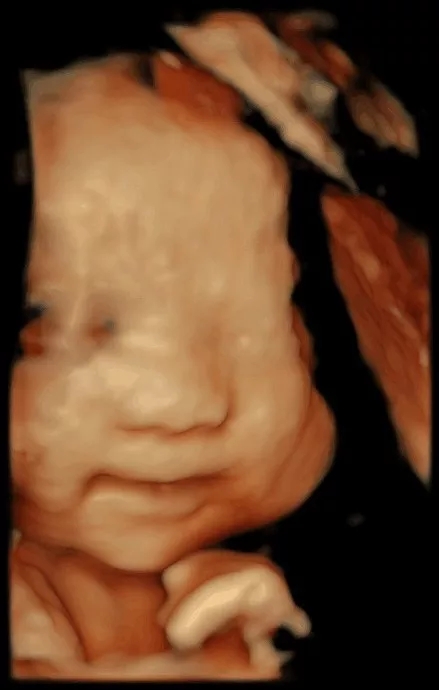

“妈妈,您昨天晚上担心我的成长发育状况,一直在做着噩梦,我很想很想跟您说,我在您腹中一直乖乖的健康成长。

我知道,妈妈您为了我健康成长,收起喜爱的化妆品与高跟鞋,告别喜爱的“垃圾”食物,每一餐都吃的精细有营养……因为我的到来,您还要承受孕吐、腰酸、水肿,承受夜里的辗转难眠。可您依旧每天满心欢喜为我准备各式各样的小衣服、小被子。

妈妈,能够做您的宝贝已经是我最大的幸福,只希望您每天都快快乐乐的!